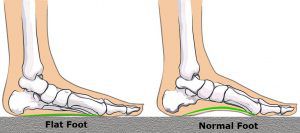

Flat foot is a condition in which the the medial or internal arch of the foot shrinks or totally disappears.

In children with flat foot, the arch of the feet disappear when standing.

To diagnose the problem, the children are asked to stand on their toes. If the arch reappears the flat foot is called flexible and no more tests or treatments are necessary.

If the arch does not form with toe-standing (rigid flat feet), or if there is pain, other tests may be needed, such as X-rays.